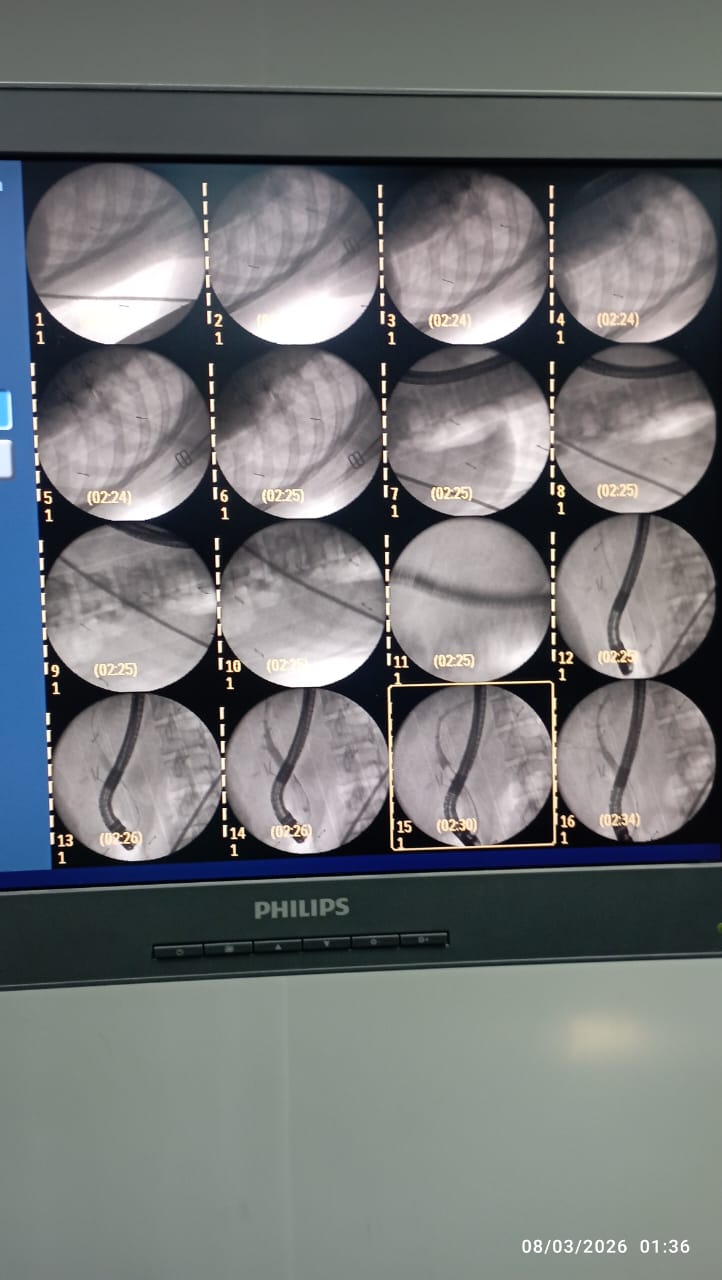

حيث تم إجراء أشعة رنين مغناطيسي على القنوات المرارية (MRCP)، والتي ساهمت في تشخيص الحالة بدقة، تلاها إجراء منظار القنوات المرارية (ERCP)، وتم من خلاله استكشاف القنوات واستخراج الحصوة المسببة للانسداد، مع توسيع القناة المرارية، كما تم استئصال المرارة بالمنظار الجراحي ضمن خطة علاجية متكاملة.